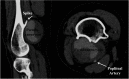

Fig. 1 (a) Multidetector computed tomography reveals a pseudoaneurysm in the right popliteal artery (10×8 cm). (b) The pseudoaneurysm (arrowheads) is closely associated with a sharp protrusion of the femoral osteochondroma.

Fig. 2 Computed tomography scan reveals a pseudoaneurysm in the right popliteal artery (4×6 cm), which is related to a protrusion of the femoral osteochondroma.